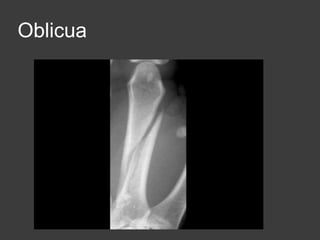

Fx diafisarias de los

metacarpianos

Transversales

Oblicuas

conminuta

Oblicua